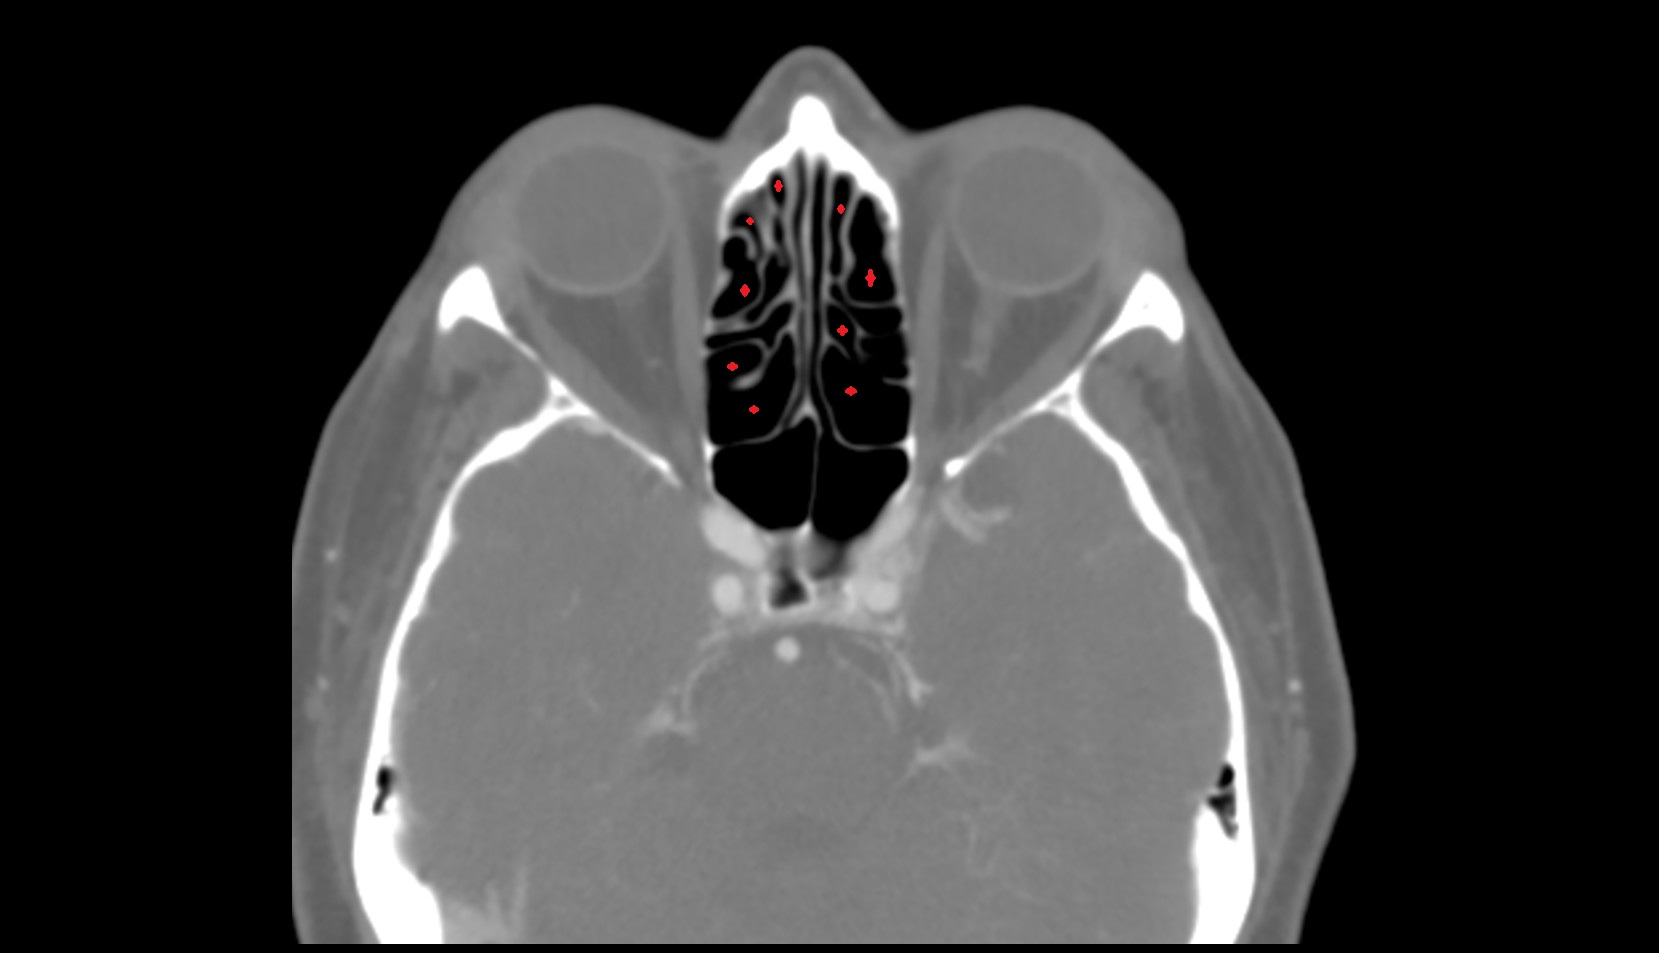

- Olfactory sulcus

- Common nasal meatus

- Inferior nasal concha

- Middle nasal concha

- Nasal septum

- Superior nasal concha